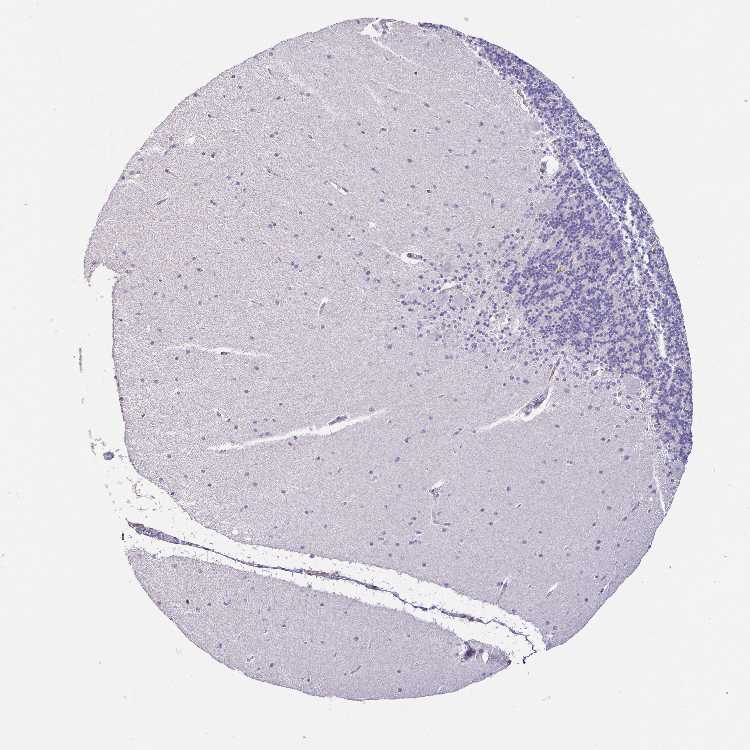

BRAIN CEREBELLUM Show tissue menu

CEREBELLUM - Expression summary

CEREBELLUM - Antibody stainingi

Antibody staining in the annotated cell types in the current human tissue is reported as not detected, low, medium, or high, based on conventional immunohistochemistry profiling in selected tissues. This score is based on the combination of the staining intensity and fraction of stained cells.

Each image is clickable and will lead to virtual microscopy that enables deeper exploration of all samples and also displays staining intensity scores, fraction scores and subcellular localization as well as patient and tissue information for each sample.

Antibody HPA005469Antibody HPA074650

Purkinje cells Not detectedNot detected

Cells in granular layer Not detectedNot detected

Cells in molecular layer Not detectedNot detected